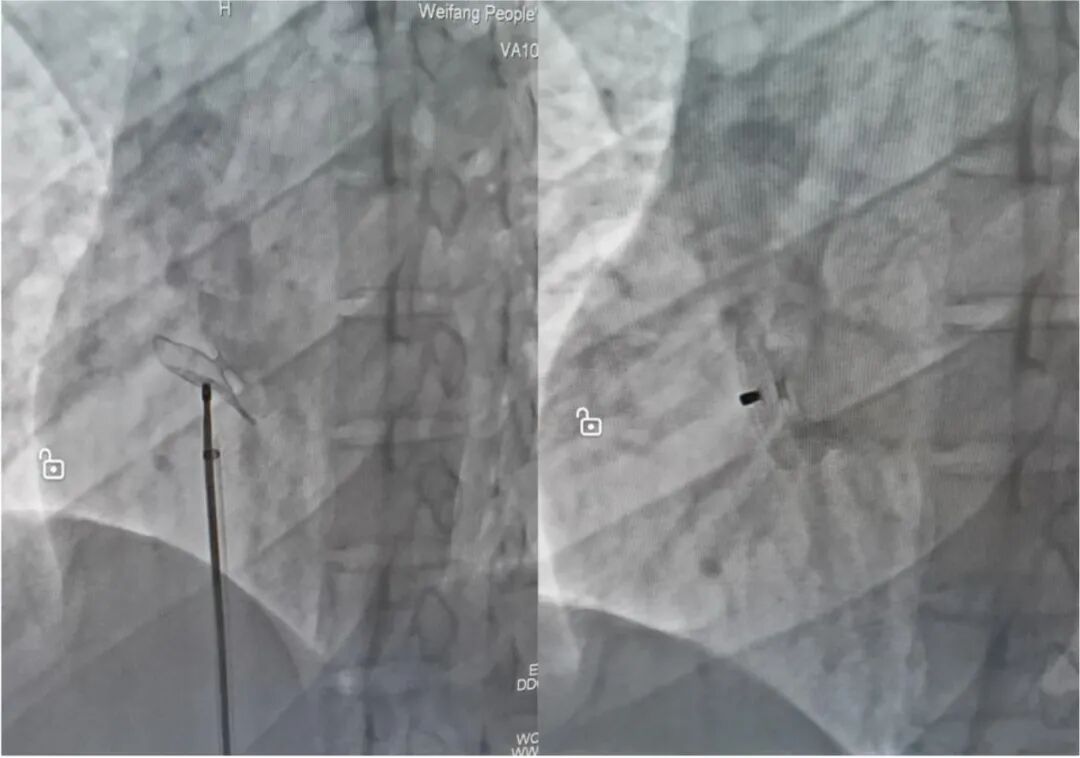

??鲁网11月30日讯 近日,潍坊市人民医院心内二科团队成功为一例卵圆孔未闭患者进行了介入封堵治疗?;颊吲?3岁,偏头痛病史半年,右心声学造影示:右心显影6个心动周期后,左心探及中量气泡,乏氏动作右心显影后,左心即刻探及大量气泡。成人患者卵圆孔未闭(PFO)听诊难以听到杂音,经胸超声心动图也难以发现,通常采用经食道超声心动图或经静脉右心导管检查才能确诊?;颊卟荒苣褪芫车兰觳?,故决定直接行右心导管探查并封堵。手术由主任医师张新才主刀,用时15分钟顺利完成。